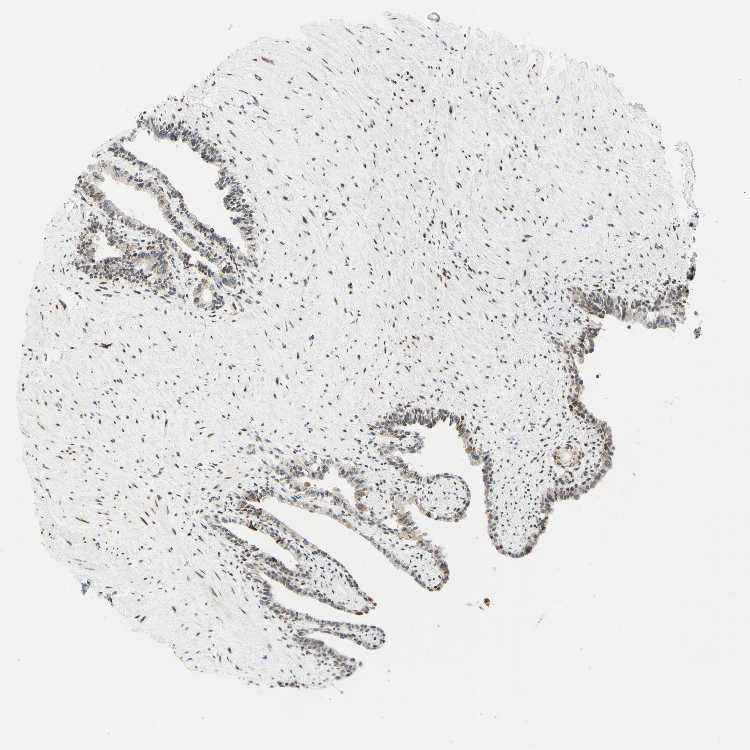

SEMINAL VESICLE - Antibody stainingi

Antibody staining in the annotated cell types in the current human tissue is reported as not detected, low, medium, or high, based on conventional immunohistochemistry profiling in selected tissues. This score is based on the combination of the staining intensity and fraction of stained cells.

Each image is clickable and will lead to virtual microscopy that enables deeper exploration of all samples and also displays staining intensity scores, fraction scores and subcellular localization as well as patient and tissue information for each sample.

Antibody HPA048677Antibody HPA056480Antibody CAB011574

Glandular cells LowNot detectedMedium